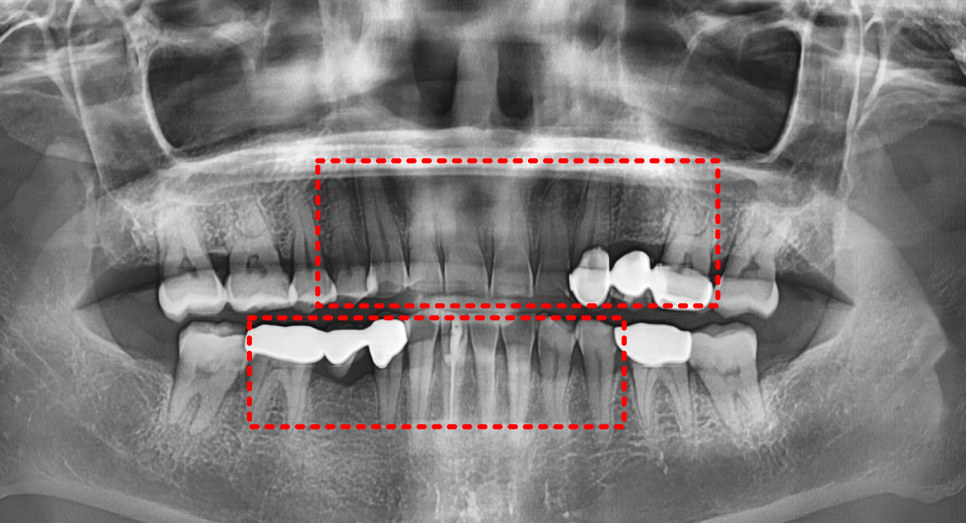

이런 분이 라미네이트를 하면 어떻게 될까요?

깨지거나 떨어질 확률이 매우 높습니다.

그래서 라미네이트보다 강도가 더 높은

지르코니아 크라운을 추천드렸습니다.

그래서 정면에서 봤을 때 중앙선이 맞지 않습니다.

게다가 왼쪽 위와 오른쪽 아래 브릿지도 오래되어 교체가 필요한 상태입니다.

여기서 중요한 점은,

이 환자분의 경우 원래 결손된 치아가 있었고,

오래된 보철물 교체가 필요했기 때문에 이러한 치료로 접근이 되었습니다.